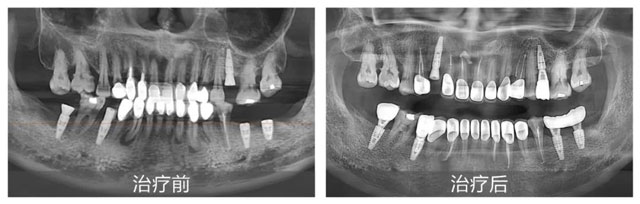

李女士治疗前后口内全景片

新桥口腔成都衣冠庙院区口腔全科医生刘宇为李女士进行了全面细致的面诊,结合全景片、CBCT、口内检查,再加上耐心的问诊,刘宇判断出李女士复杂的口腔状况:四环素牙、死髓牙相关性基牙颜色异常,牙冠边缘牙体龋坏发黑变色,严重影响美观;存在牙齿长期龋坏、牙神经发炎、根尖发炎等问题;而牙龈红肿出血、松散萎缩等牙周病问题更是让她的口腔状况雪上加霜。

李女士的口腔状况较为复杂,所涉问题横跨多个学科领域,修复治疗、口内治疗、牙周治疗需同时兼顾,这无疑是对医生综合能力的考验。刘宇医生凭借丰富的临床经验,为李女士量身定制了一套全面、科学的整体治疗方案。首先通过根管治疗消除根尖炎症,针对牙周病展开系统治疗,待牙龈恢复健康状态后,最后制作新的牙冠,全方位改善牙齿的外观与功能。此外,在牙龈恢复至健康状态前,考虑到李女士的日常用牙需求,刘医生特意为她安装了临时牙冠,让李女士在治疗期间也能正常饮食,尽可能减少治疗对生活的影响。